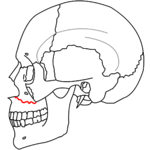

- Le Fort I fracture (horizontal), otherwise known as a floating palate, may result from a force of injury directed low on the maxillary alveolar rim, or upper dental row, in a downward direction. The key component of these fractures, in addition to pterygoid plate involvement, is involvement of the lateral bony margin of the nasal opening. They also involve the medial and lateral buttresses, or walls, of the maxillary sinus, traveling through the face just above the alveolar ridge of the upper dental row. At the midline, the inferior nasal septum is involved. Historically, it has also been referred to as a Guérin fracture, although this name is less commonly used in practice.

Treatment is surgical, and usually is able to be performed once life-threatening injuries are stabilized, to allow the patient to survive the general anesthesia needed for invasive orthopedic restructuring. First a frontal bar is used, which refers to the thickened frontal bone above the frontonasal sutures and the superior orbital rim. The facial bones are suspended from the bar by open reduction and internal fixation with titanium plates and screws, and each fracture is fixed, first at its superior attachment to the bar, then at the inferior attachment to the displaced bone. For stability, the zygomaticofrontal suture is usually replaced first, and the palate and alveolar ridge are usually fixed last. Finally, after the horizontal and vertical maxillary buttresses are stabilized, the orbital fractures are fixed last.[5]